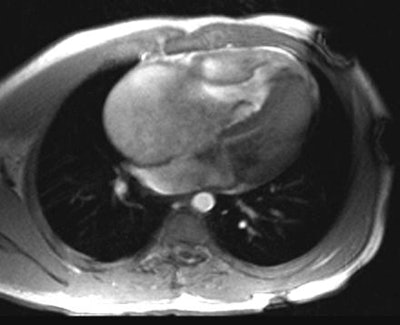

Ebstein's Anomaly:

The axial cine-GRE MR image on the left was obtained at end-systole and the right image at end-diastole. There is massive right atrial enlargement and the tricuspid valve leaflets are extremely long, extending down nearly to the right ventricular apex. There is marked "atrialization" of the right ventricle; and there is almost no coaptation of the valve leaflets during systole.